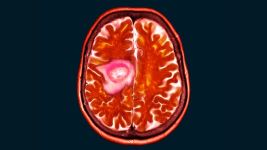

Glioblastom: Uzroci, simptomi i mogućnosti lečenja

Šta je glioblastom (GBM)?

Glioblastom je agresivni tumor mozga s raznim simptomima. Uzroci su različiti, a faktori rizika uključuju starost i genetske...